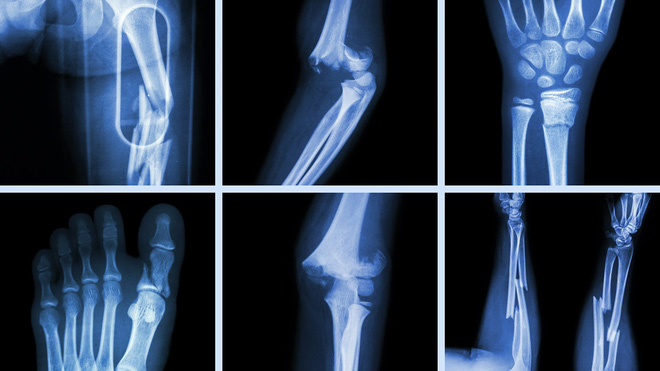

Ngoài ra, để biết chắc xương có gãy hay bị rạn hay không, bạn phải đến bệnh viện để chụp X-quang.